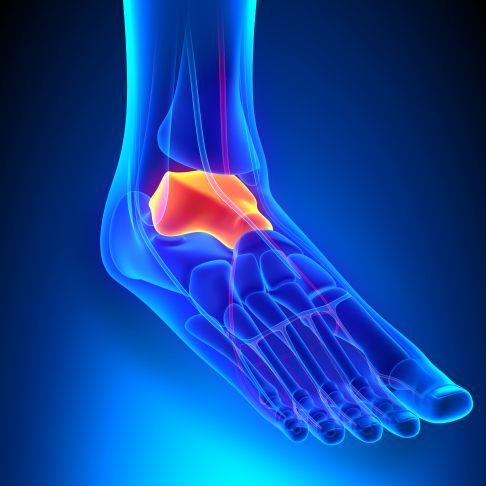

Bei einer Talusnekrose wird das Sprungbein (Talus) nicht mehr ausreichend durchblutet und stirbt ab. Das Sprungbein ist ein Fußknochen, das zusammen mit Schienbein (Tibia) und Wadenbein (Fibula) das obere Sprunggelenk (OSG) bildet. Schien- und Wadenbein umfassen dabei das Sprungbein passgenau wie eine Zange - man spricht auch von der Sprunggelenksgabel (Malleolengabel).

Der Talus nimmt unter den Fußknochen eine Sonderstellung ein. Das Sprungbein besitzt keine Sehnen und keinen Muskelansatz. Ausschließlich Bänder an benachbarten Knochen halten das Sprungbein in seiner Position. Eine zusätzliche Durchblutung und Versorgung des Knochengewebes durch Sehnenansätze existiert nicht.

Zwischen Taluskörper und Taluskopf liegt der Talushals. Er bildet das Dach des Sinus tarsi, eines Knochentunnels zwischen Fersenbein (Calcaneus) und Talus. Der Sinus tarsi dient als Eintrittsstelle für Blutgefäße in den Talus. Die Durchblutung wird überwiegend über diese Gefäße sichergestellt.

Oberhalb des Talus mit der aufliegenden Sprunggelenksgabel liegt das obere Sprunggelenk (OSG). Distal grenzt der Talus an das Fersenbein (Calcaneus), mit dem er über das talocalcaneare Gelenk verbunden ist. Dieses Gelenk bildet den hinteren Teil des unteren Sprunggelenks. Nach vorne steht der Taluskopf mit dem Kahnbein (Os naviculare) in gelenkiger Verbindung. Hier sind drei Gelenkflächen an der Gelenkbildung beteiligt. Durch diese besondere Anatomie ist ein Großteil der Talusoberfläche mit Knorpel bedeckt.